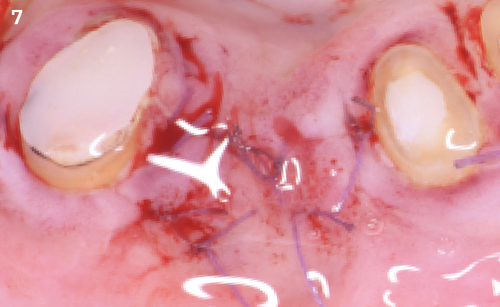

Following the extraction of tooth 42, a drug-induced osteonecrosis was diagnosed and treated. One week after the treatment, the clinical picture had improved and the symptoms were significantly reduced.

Approach & Result